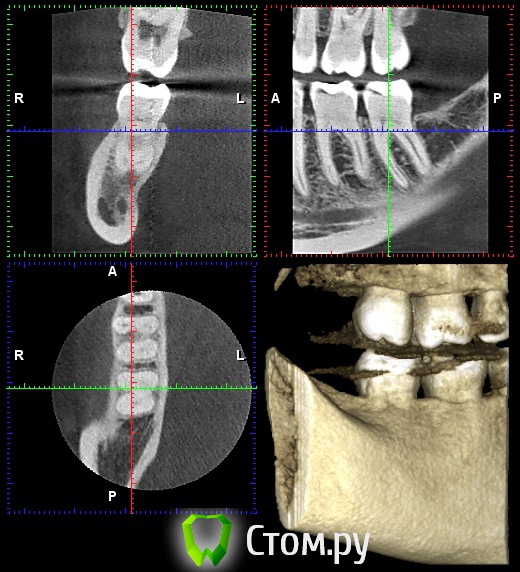

Обратилась на форум , посоветовали сделать КТ и предположили хроническое воспаление в зубе  или еще как вариант проблема с суставом.

Обратилась повторно к другому стоматологу после того , как сделала КТ.

Такие результаты : сказали , что оснований для удаления нерва нету , на снимке с зубами все хорошо.

Прикрепляю свой снимок. Спасибо